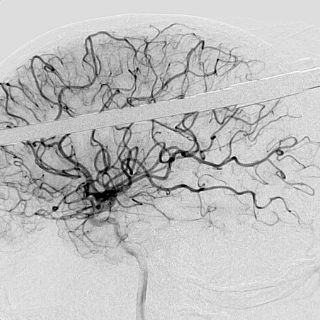

GUADALAJARA, JALISCO (26/MAY/2013).- La psicóloga y psicoterapeuta Xóchitl Trillo dijo que el cerebro, a lo largo de la vida, está propenso a sufrir distintas lesiones debido a traumatismos, accidentes, secuelas de tumores, e incluso por factores como el estrés.

Añadió que las secuelas pueden ser déficits motores, sensoriales y neurocognoscitivos, que requerirán rehabilitación física y psicológica, por lo que la recuperación funcional dependerá del daño cerebral.

Señaló que las lesiones cerebrales también son conocidas como infartos cerebrales o embolias.